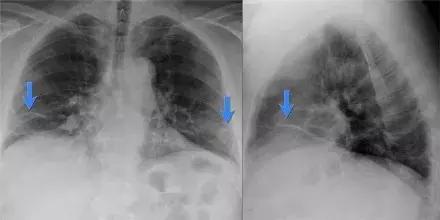

影像表现:

➢ 右心缘模糊(轮廓征)

➢ 中叶萎陷造成三角形阴影

➢ 右叶不张一般不会引起右膈显著升高

➢在后前位胸片上,漏斗胸很像中叶不张,侧位片可有助于鉴别诊断